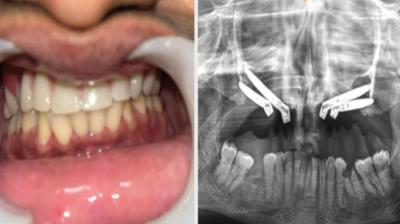

एम्स भोपाल डेंटल टीम ने लिखा इतिहास, इंटरनेशनल जर्नल में केस भेजा

6 Sep, 2025 10:00 PM IST | NEWSALERTINDIA.COM

एम्म में जटिल सर्जरी को सफलतापूर्वक अंजाम दिया है। इस सर्जरी में ट्यूमर के कारण काटे गए निचले जबड़े को पैर की हड्डी से दोबारा बनाया गया और उसमें 13...